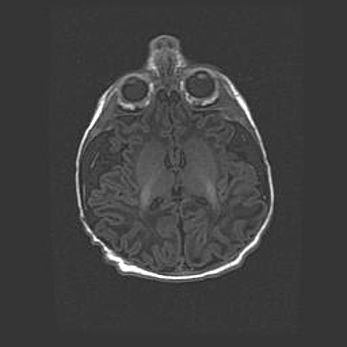

Церебральная ишемия II.

Возраст: 5 дней

Вес: 3400 г

Пол: женский

Окружность головы: 35 см

Срок гестации: 39 недель

Церебральная ишемия – это заболевание, характеризующееся недостаточностью (гипоксией) либо полным прекращением (аноксией) снабжения мозга кислородом по причине закупорки одного или нескольких сосудов. Это приводит к  что метаболическим расстройствам различной степени тяжести в тканях головного мозга, развитию коагуляционных некрозов и гибели нейронов.